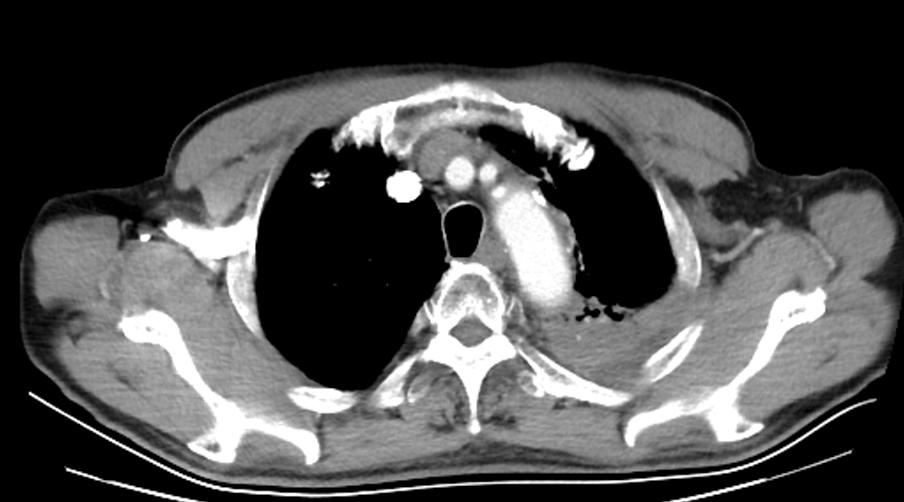

2019-10-16 胸腹部CT示:左肺上叶占位并周围阻塞性炎症、节段性肺不张,纵隔及双肺门多发小及增大淋巴结。肝内小囊性灶,建议增强扫描。考虑双侧壶腹型肾盂。前列腺増生、钙化。肠壁多发钙化:考虑血吸虫性肠道改变。

2021-09-29胸腹部CT示:检查结果左肺上叶占位并周围阻塞性炎症、节段性肺不张:较前进展,相应左肺上叶肺动脉受侵,纵隔及双肺门多发小及增大淋巴结,建议继续治疗及复查。支气管炎、肺气肿伴双肺多发肺大泡同前,右肺下叶少许炎症、右侧胸膜增厚同前,左测少许胸腔积液,建议复查。左侧第4肋骨质破坏,建议结合全身骨扫描。主动脉及部分冠脉钙化灶。左侧颈背部皮下囊性灶较前相仿,建议结合临床。肝内小囊性灶同前;前列腺増生、钙化。提示血吸虫性肠病,建议结合临床病史。